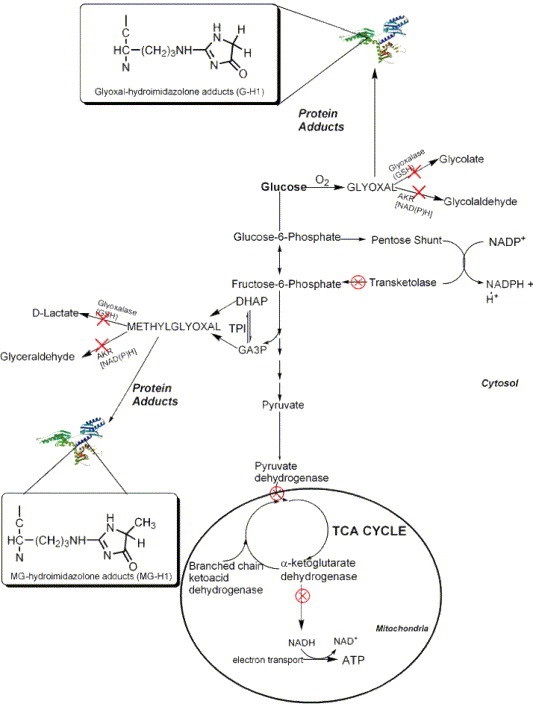

There is a truism in the sociology of occupational knowledge: “If all a doctor has is a hammer, then everything becomes a nail”. All modern medicine relies on overkill dosages of drugs or surgery as the standard of care (Jennifer Daniels, MD, The Lethal Dose, 2013). There are no drugs or surgery that can alleviate the symptoms of poisoning from a natural pesticide found in plant foods but also produced in the liver. With this professional void, treating oxalosis has mainly been left to nutritionists. So, if you ask a nutritionist about oxalates, you will get a predictable answer to reduce oxalates in your diet. This is insufficient because most oxalates are produced by poor metabolism in the liver. Oxalate is a natural pesticide found in plant foods, but also is internally produced mainly from fungus and vitamin C (see How Oxalates Ruin Your Health). Oxalosis manifests as a syndrome of three main symptoms: oxalate crystals in tissues and kidney; histamine, mucous attack in nasal passages; and pseudo-gout mainly from acidity and eating cooked meat.

Endogenous Oxalates Mainly Begin in the Liver

Killer Proteins and Oxalosis

I shall try to show how oxalosis is related to excess unmetabolized protein in the human body. Beiler asserts “proteins can be body killers if we are not watchful of our diet”. Protein is necessary to grow and repair the body. However, poor metabolism with age often leads to making metabolites (non-nutrients) from fat, protein, or carbohydrate (not just from dietary oxalate consumption). Excess protein is one of the main sources of acidosis, which can be life threatening in the blood stream but not in the urine or saliva. Protein can change into fat or carbohydrate, but fat and carbs cannot morph into protein (Beiler).

My thesis is that internally produced oxalate is systemic and organic. It mainly manifests oxalosis (oxalate poisoning) and is produced in the liver, not solely from dietary oxalate, which can be managed with modest palliative measures. Oxalosis comes from poor elimination in the liver and not entirely from the food we consume. It is an interaction between the two in a feedback loop. I believe that the conventional approach to oxalosis, e.g. reducing the consumption of high oxalate foods, does not significantly reduce internal oxalate production, and thus, is merely palliative.

The motivation for this paper is that I could find no satisfactory explanation of the mechanism of action for endogenous oxalate other than vague references that it is produced in the liver, while dietary oxalosis happens in the kidney. Hereinabove I have hypothesized a plausible explanation of oxalosis from the liver from poor protein metabolism and oxidation. Since science is not just about finding evidence, but also about attempting to falsify a hypothesis, I am throwing this hypothesis out there for open refutation and clarification.